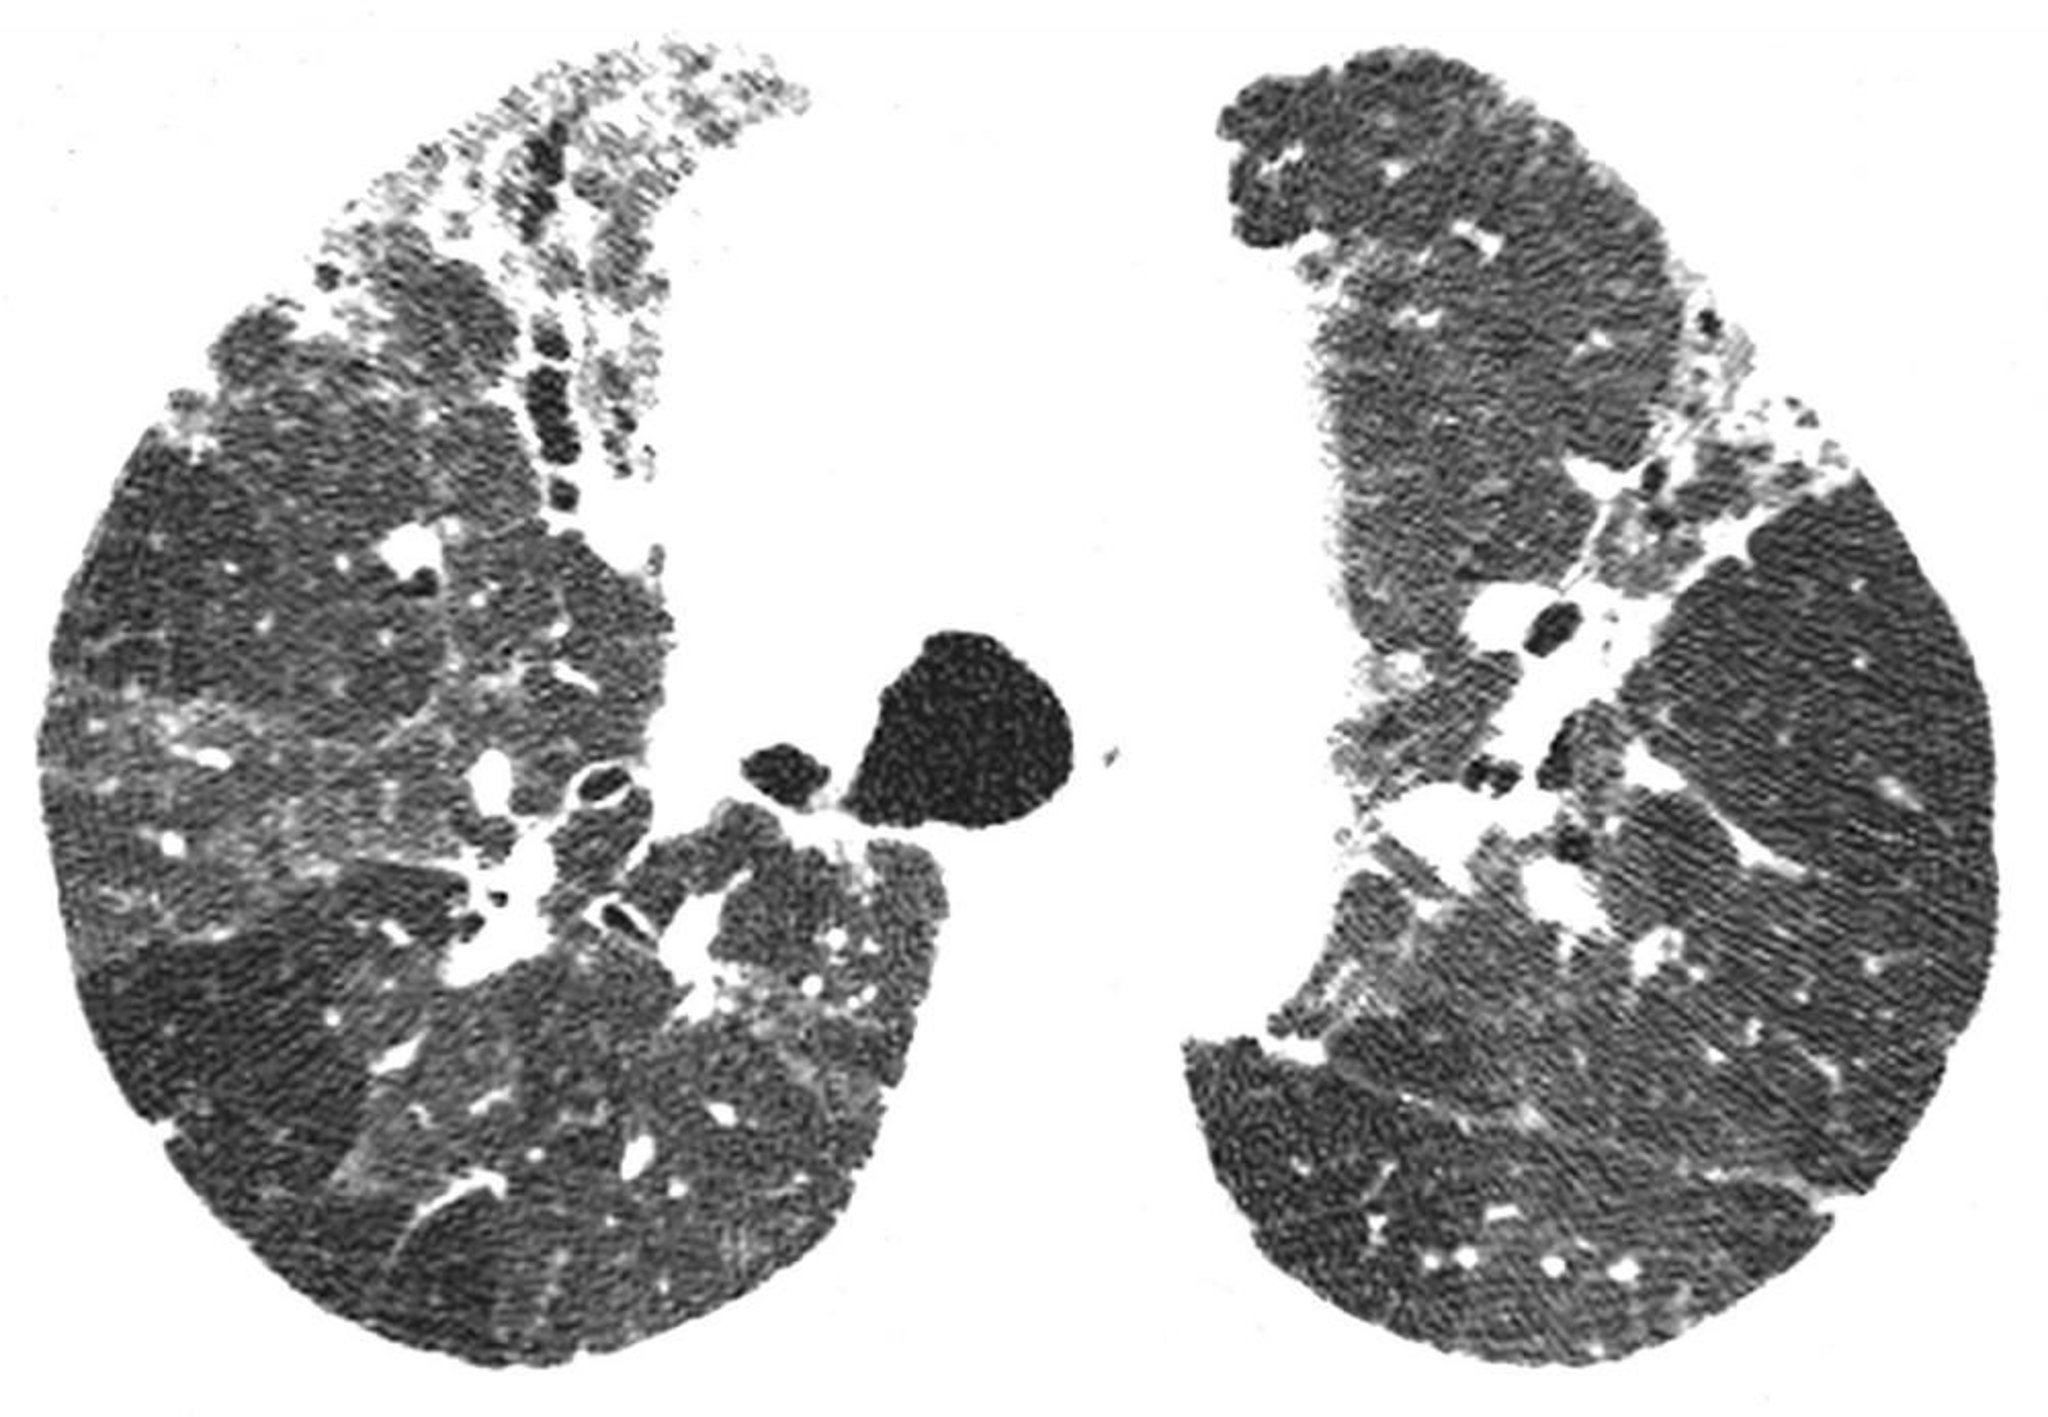

Polmonite da ipersensibilità cronica

La TC ad alta risoluzione mostra i segni di fibrosi, inclusi reticolazione irregolare e bronchiectasie da trazione. Le aree con ridotta densità polmonare sono compatibili con le regioni con ostruzione delle vie aeree. Questa combinazione di risultati è indicativa per polmonite da ipersensibilità.

Image courtesy of Harold R. Collard, MD.